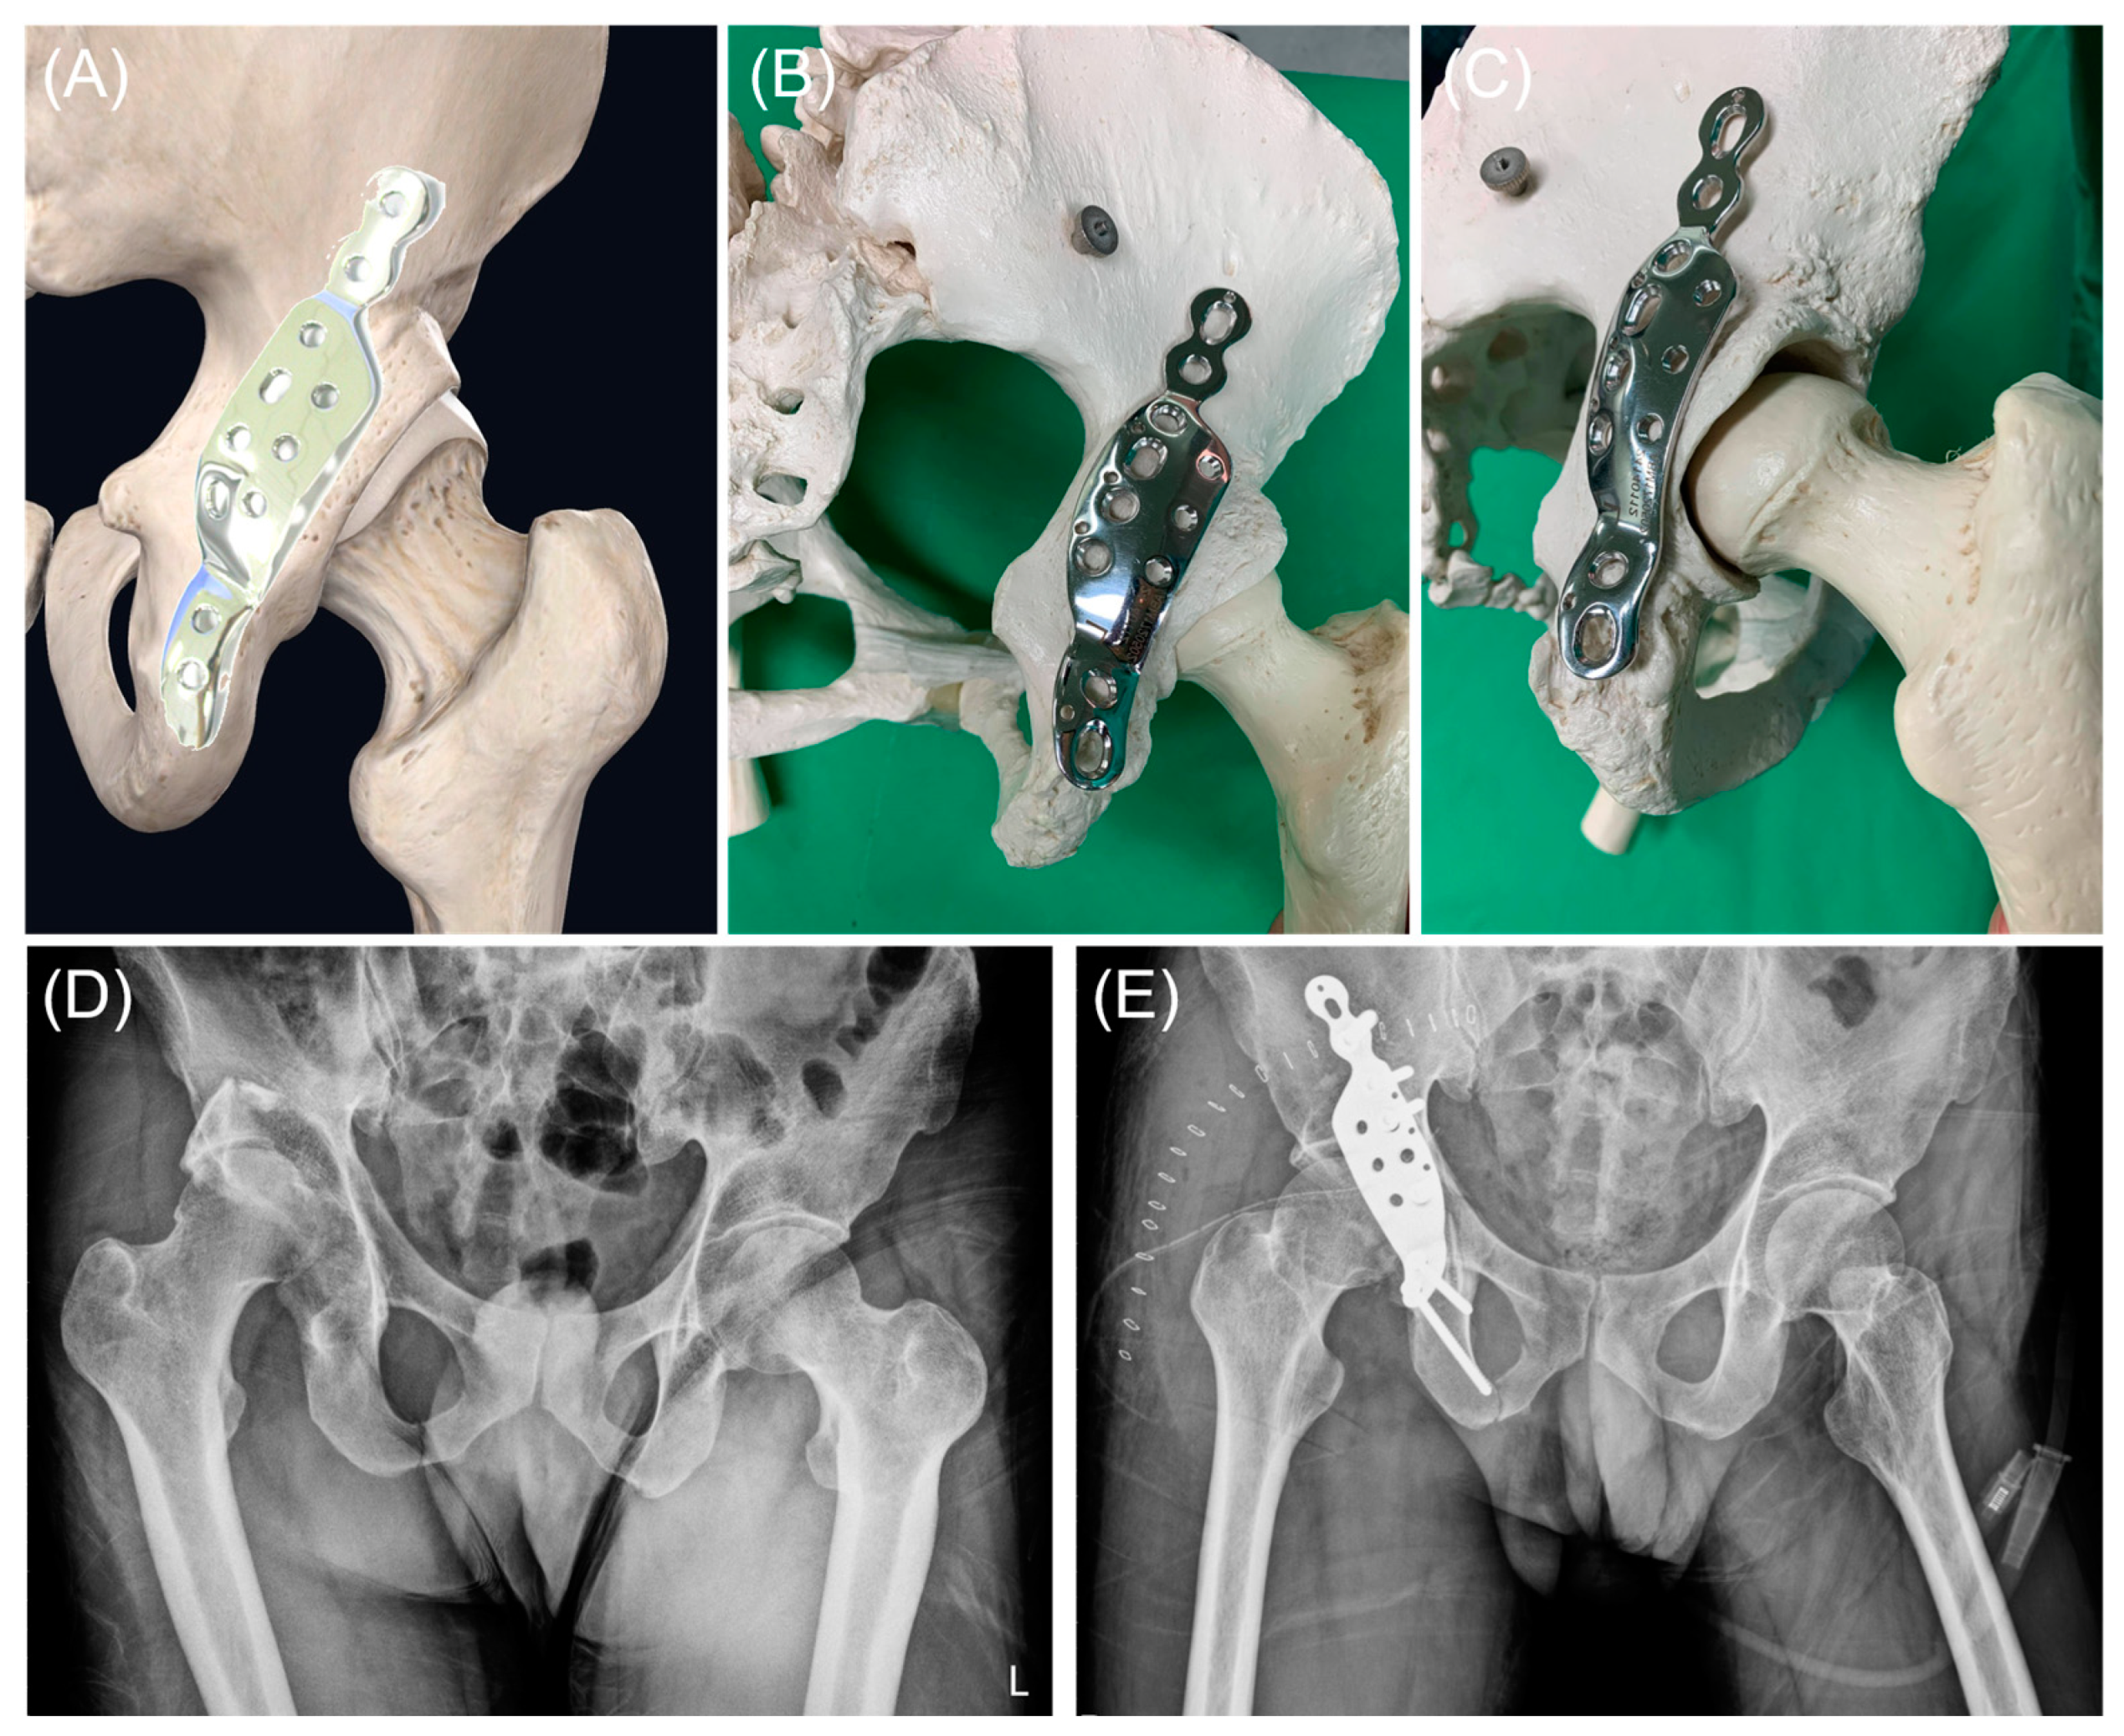

2.3. Implant Design

2.4. Surgical Procedure